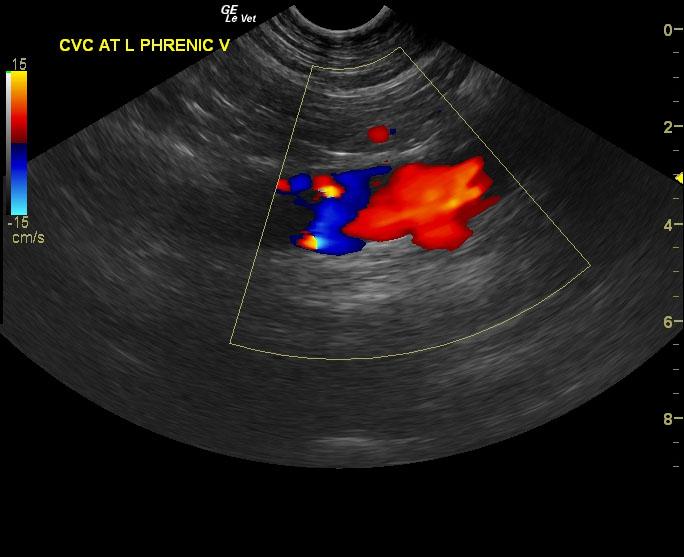

The right adrenal gland was isoechoic to surrounding fat. It measured 2.1 x 0.9 cm. The left adrenal gland comprised a 7.9 x 5.3 cm strongly vascular mass noted on power flow Doppler. Invasion into the left phrenicoabdominal vein was noted. However, the vena cava was not invaded at this time.